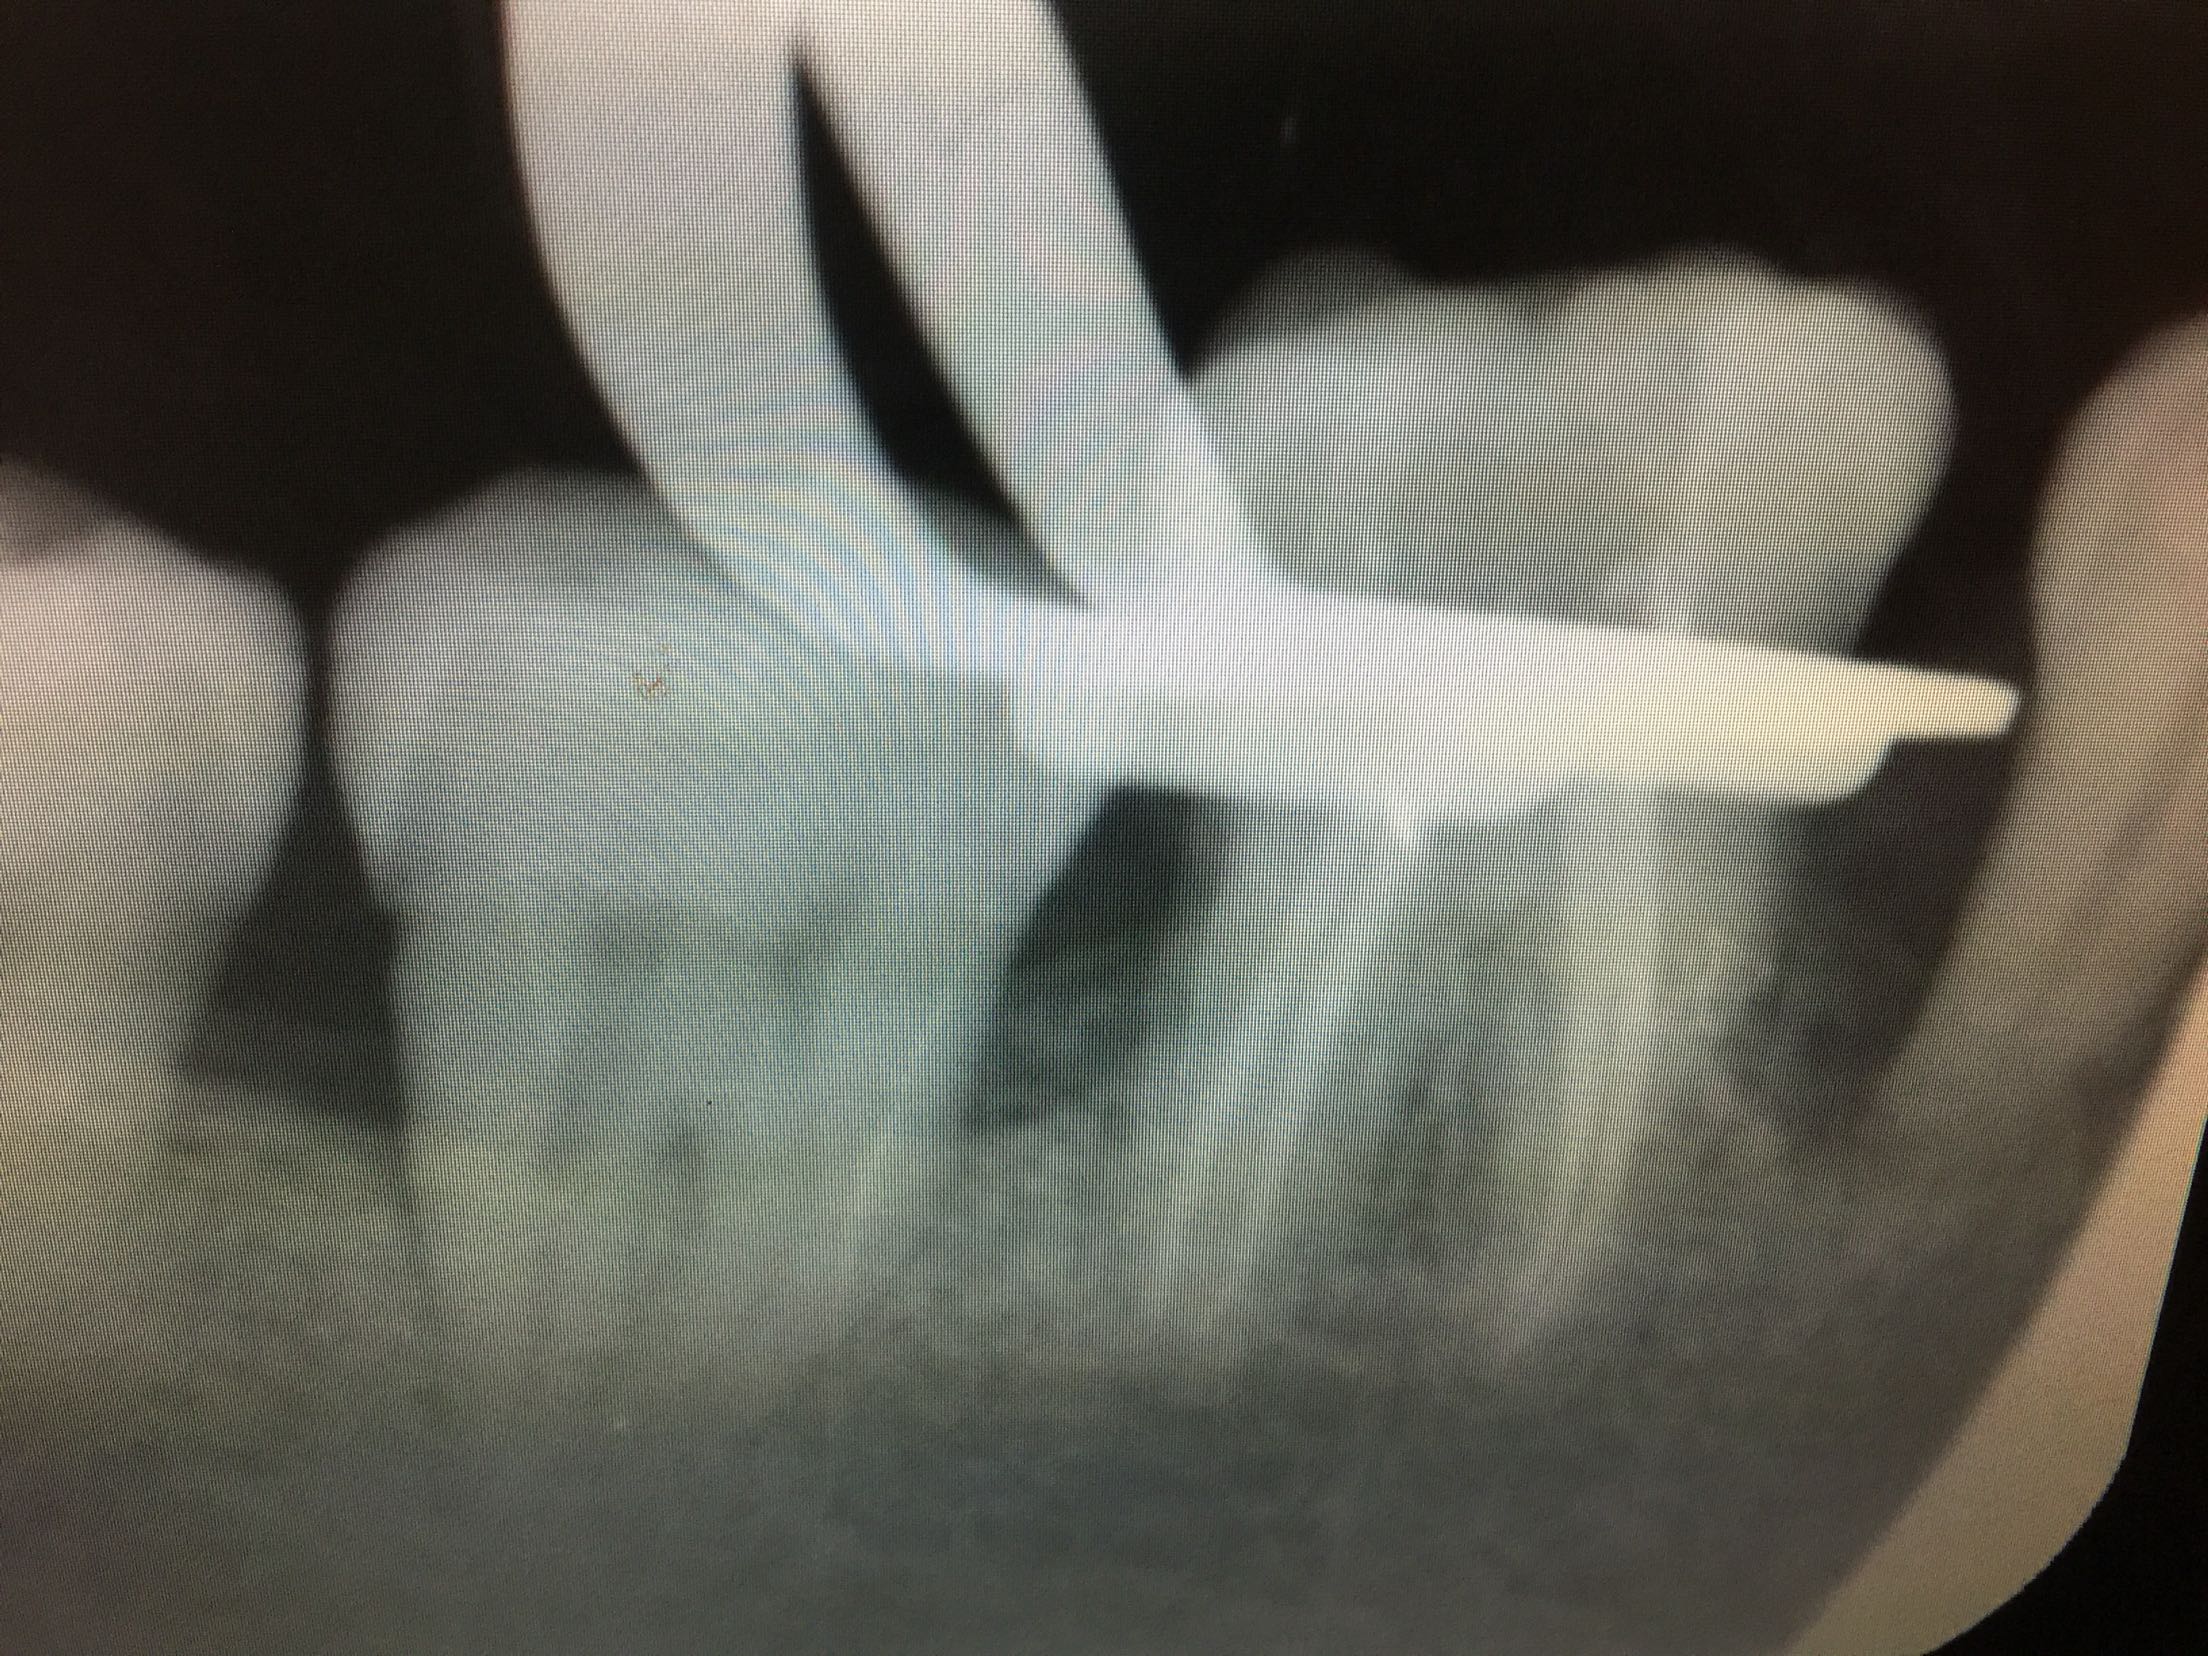

检查:全口卫生差,牙石++,软垢+,牙龈红肿,有退缩。口内多颗牙缺失,46牙伸长,松-+。 X线:46牙伸长,未行根管治疗,根尖区未见暗影。

诊断:46牙伸长 全口牙周炎 牙列缺损 治疗计划:46牙去髓术 全口洁治 择期修复缺牙区 治疗:碧蓝麻局部浸润,46牙去净龋坏,开髓揭髓顶,探查根管4根,牙髓摘除术,k挫初步预备,根管测长仪测量根管长度,各根管内导入根管润滑剂EDTA,Protaper镊钛器械预备根管,冲洗,超声荡洗,水溶性氢氧化钙充填根管,暂封,约复诊。 复诊:一周后,诊间无不适,46牙暂封完好,冷-,探-,叩-,不松。 试主尖,